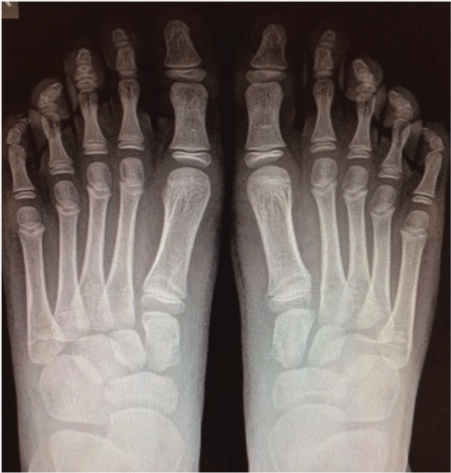

The patient complained of bilateral pain of mid medial foot after physical activities, mainly at the end of the day. The first onset of symptoms was described as a discomfort, worsened with activity and relieved with rest. Physical examination reflected an otherwise normal healthy young boy, with normal weight. No edema, soft-tissue swelling, or discoloration was observed at the feet (Figure 1 and Figure 2). Full range of motion of all joints was accomplished without any pain. Careful palpation of the medial dorsal aspect of the midfoot reproduced the patient's pain. Laboratory tests like a complete blood count, erythrocyte sedimentation rate (ESR) and C-reactive protein (CRP) were normal. Radiographical studies showed a bilateral irregular outline and an increased density of medial cuneiforms and tarsal scaphoids (Figure 3 and Figure 4). No significant changes were noted in the other bones of the feet. MRI was not carried out. The patient was treated with acetaminophen, a mild analgesic, and limitation of physical activity. He was able to carry out normal activities with the help of custom orthosis to support the arch in order to reduce the pain, but he had to refrain from sports.

.

Figure 3: X-ray lateral view at first examination (Higher arrows: osteochondrosis of the medial cuneiform; Lower arrows: osteochondrosis of tarsal scaphoid).

View Figure 3

Figure 4: X-ray dorsoplantar view at first examination (Higher arrows: osteochondrosis of the medial cuneiform; Lowest arrows: osteochondrosis of tarsal scaphoid).

View Figure 4